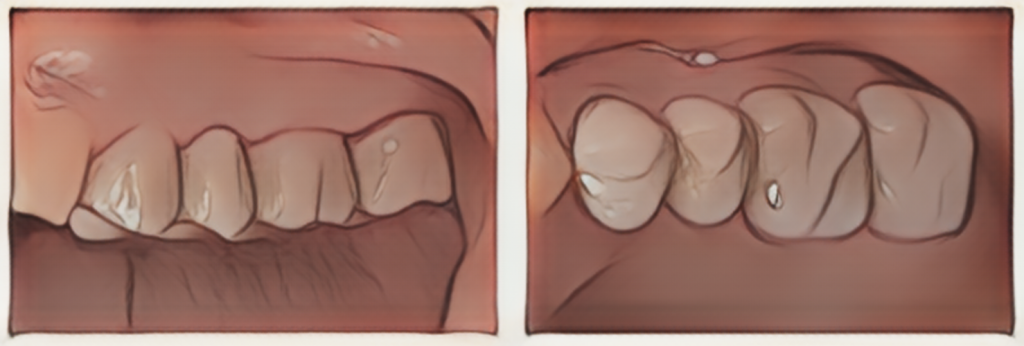

プロビジョナルレストレーションと言われる治療用義歯を装着し、機能性や清掃性の評価を行いました。1.1万円/本

同様にフルジルコニアブリッジ修復を行った症例です。